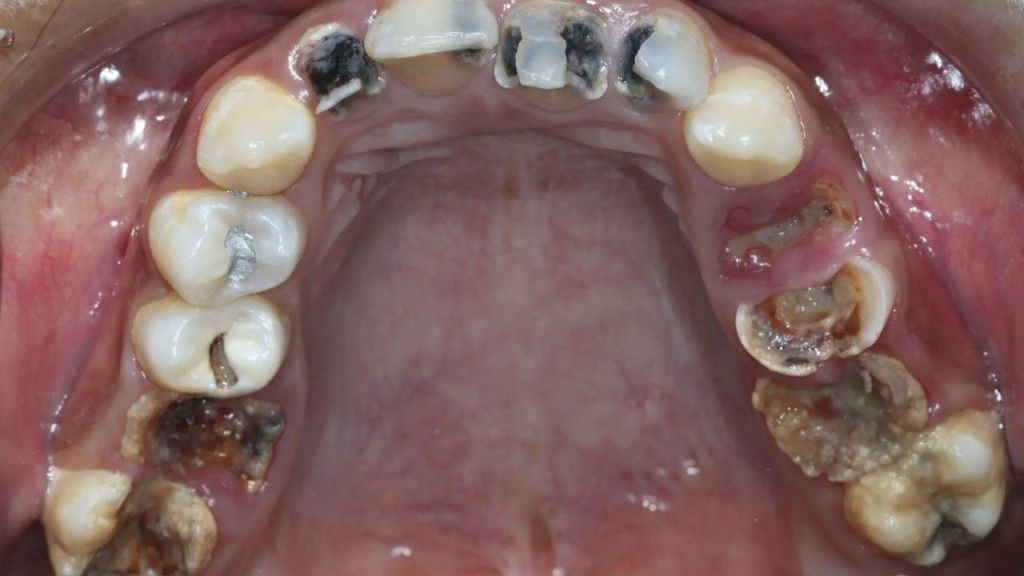

Diş çürükleri, günümüzün en yaygın sağlık sorunlarından birini oluşturan, dişlerin yapısal bozulmasına yol açan bir hastalıktır. Bu durum, genellikle diş minesinin asidik maddelerle aşındırılması sonucunda oluşur. Diş çürükleri, başlangıçta hafif bir rahatsızlık gibi görünse de, tedavi edilmezse dişin kaybına ve ciddi sağlık sorunlarına yol açabilir. Diş çürüğünün nedenlerini anlamak ve bu durumu önlemek için bilinçli olmak oldukça önemlidir. İşte diş çürüklerinin nedenleri ve bunların önlenmesi için alınabilecek önlemler.